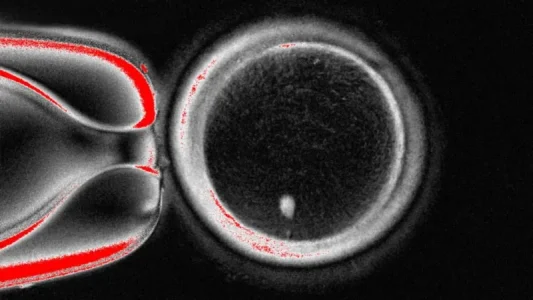

ओरेगन हेल्थ एन्ड साइन्स युनिभर्सिटीको अनुसन्धान टोलीले मानिसको छालाको कोषबाट सम्पूर्ण आनुवंशिक कोड भएको केन्द्रक निकाल्छ । यसलाई आफ्ना आनुवंशिक निर्देशनहरू हटाइएको दाताको अण्डाभित्र राखिन्छ । अहिलेसम्म, यो प्रविधि सन् १९९६ मा जन्मिएको विश्वको पहिलो क्लोन स्तनधारी ‘डल्ली’ भेडा बनाउन प्रयोग गरिएको जस्तै छ ।

तर, यो अण्डा शुक्रकीटद्वारा निषेचित हुन तयार हुँदैन किनभने यसमा पहिले नै पूर्ण क्रोमोजोमहरू हुन्छन् । सामान्यतः, आमाबाबुबाट २३-२३ वटा डीएनएका बन्डलहरू (क्रोमोजोमहरू) प्राप्त गरी कुल ४६ वटा हुन्छन् । त्यसैले अर्को चरणमा अण्डालाई आफ्ना आधा क्रोमोजोमहरू त्याग्न लगाइन्छ, जसलाई अनुसन्धानकर्ताहरूले ‘माइटोमियोसिस’ नाम दिएका छन् (यो माइटोसिस र मेयोसिस, कोष विभाजनका दुई तरिकाको संयोजन हो) ।

नेचर कम्युनिकेसन्स जर्नलमा प्रकाशित अध्ययनले ८२ वटा कार्यक्षम अण्डाहरू बनाइएको देखाएको छ । ती अण्डाहरूलाई शुक्रकीटसँग निषेचित गरियो र केही भ्रूण विकासको प्रारम्भिक चरणमा पुगे । कुनै पनि ६ दिनको चरणभन्दा अगाडि विकसित भएनन् ।